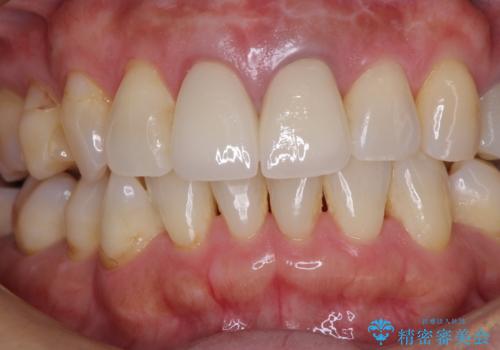

- 治療中の前歯の仮歯がひどい状態であるとのことで来院された患者様です。

治療中の前歯は根管治療の途中であり、根尖部に痛みを感じる状態でした。

まずは審美的な仮歯を装着し、根管治療を行った後にオールセラミッククラウンにて補綴治療を行うこととしました。

根管治療後に痛みは軽減しましたが、僅かな痛みが続くとのことで、レントゲン写真では病変は認められなかったものの、歯根端切除を行うこととしました。処置後は痛みは全くなくなり、安心して補綴治療を行うことができました。